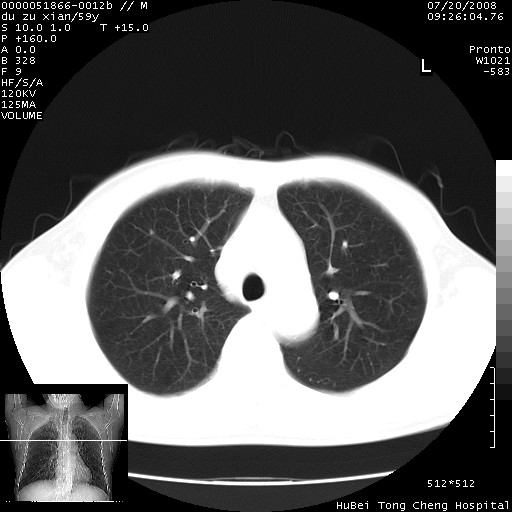

以下是引用宇宙ct在2008-8-25 23:21:00的发言:[br]右肺周围性肺癌并肋骨转移,纵隔淋巴结转移。

以下是引用zsl6918在2008-8-25 22:40:00的发言:[br]右肺周围性肺癌并肋骨转移,纵隔淋巴结转移。

以下是引用zy_zj在2008-8-26 15:24:00的发言:[br]单从病变本身,我倾向良性炎性病变,但肋骨转移了,所以说是考虑右肺周围性肺癌并肋骨、纵隔淋巴结转移可能性大。